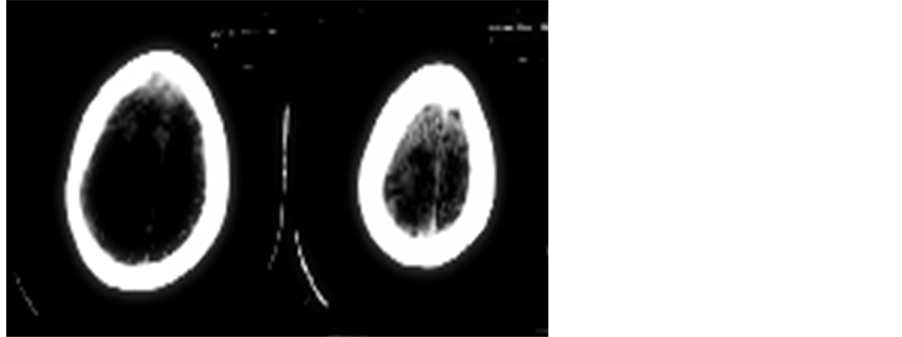

The CT Brain was suggestive of left sided cerebral hemiatrophy with epsilateral enlargement of lateral ventricle (Ventriculomegaly); features suggestive of Dyke Davidhoff Masson Syndrome (DDMS) (See Figure 1 & Figure 2). MRI brain with MR angiography was done to confirm the diagnosis and delineate the arterial system after stabilization.

Figure 2. CT brain image showing left cerebral hemiatrophy.